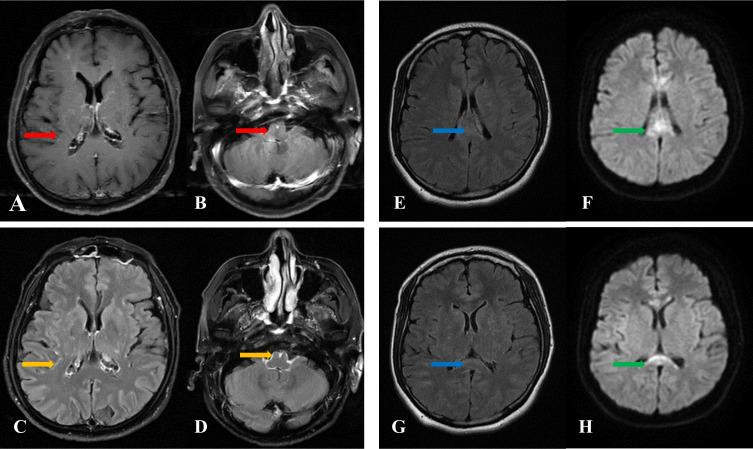

The predominant GFAP-A clinical manifestations are limb weakness/numbness and fever. GFAP-A has a propensity in the early stage for meningeal and leptomeningeal lesions on the brainstem surface, with a typical pattern of periventricular linear radial and leptomeningeal enhancement. The clinical manifestations and leptomeningeal enhancement were rapidly alleviated after treatment with high doses of corticosteroids or/and intravenous immunoglobulin, although, there are patients who may present with increased brain parenchymal lesions. On 3T MRI, the spinal cord demonstrated extensive longitudinal T2-weighted hyper-intensity, central distribution, and gray matter involvement. Optic nerve involvement in some patients was also noted with optic nerve swelling and abnormal enhancement. In addition to the classic reversible splenium of corpus callosum syndrome (type I), this study found the much rarer type II with diffusion restriction on DWI (Diffusion Weighted Imaging) in the corpus callosum. Positive anti-GFAP antibodies in serum or cerebrospinal fluid (CSF) are important for GFAP-A diagnosis with overlapping antibodies commonly noted. This study found anti-GM3 antibodies, a rare finding also previously reported.

GFAP-A的主要临床表现为肢体无力/麻木和发热。GFAP-A在早期倾向于脑干表面的脑膜和软脑膜病变,具有典型的脑室周围线性放射状和软脑膜强化模式。高剂量皮质类固醇或/和静脉注射免疫球蛋白治疗后,临床表现和软脑膜强化迅速缓解,尽管有些患者可能出现脑实质病变增加。在3T MRI上,脊髓表现为广泛的纵向T2加权高信号、中央分布和灰质受累。部分患者还出现视神经受累,表现为视神经肿胀和异常强化。除了经典的胼胝体压部可逆综合征(I型)外,本研究还发现了胼胝体在扩散加权成像(DWI)上有扩散受限的更为罕见的II型。血清或脑脊液(CSF)中抗GFAP抗体阳性对GFAP-A诊断很重要,常见有重叠抗体。本研究发现了抗GM3抗体,这也是先前报道的罕见发现。